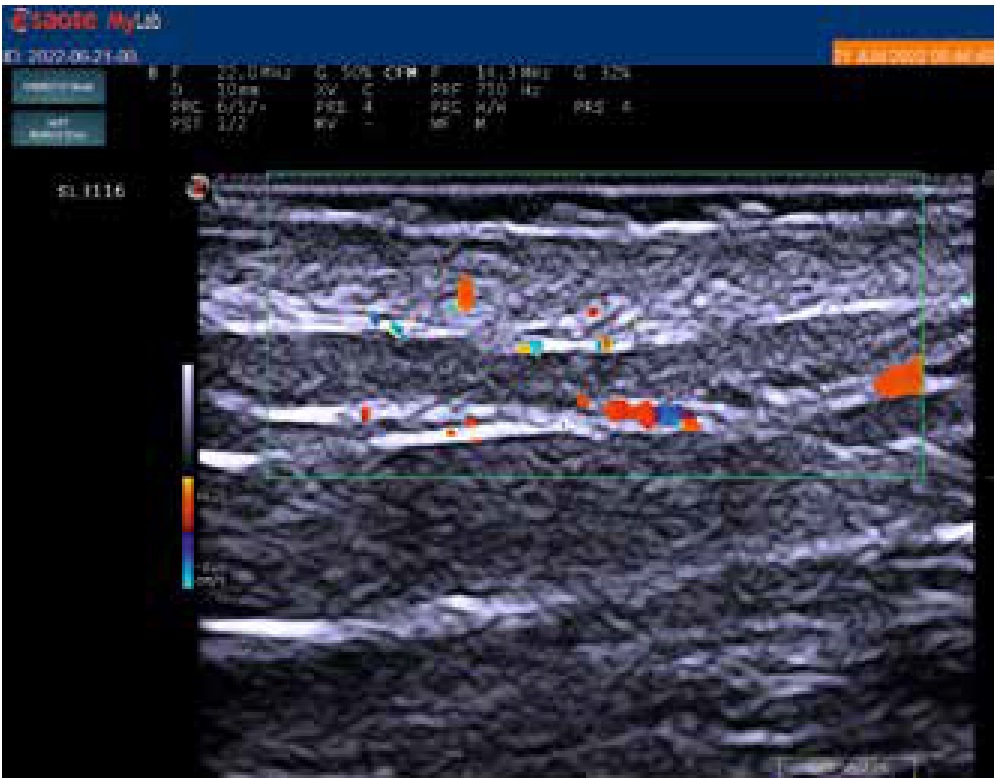

При оценке первичного энергетического допплерографического ультразвукового исследования кожи в области псориатических бляшек были отмечены признаки повышения кровотока в сосочковом и сетчатом слоях кожи в виде множественных изолированных и сливных допплеровских сигналов по сравнению с отсутствием подобных сигналов в неповрежденной коже (рис. 2 и 3). У большинства обследованных больных (47 больных, 57,3%) наблюдались признаки 2-й (умеренной) степени повышения кровотока, у 23 (28%) больных — 1-й (минимальной) степени и у 12 (14,6%) больных — 3-й (выраженной) степени. Среднее значение шкалы градации степени повышения допплеровского энергетического кровотока у обследованных при первичном исследовании составило 1,87.

Рис. 2. Крупные допплеровские сигналы сливного характера в дерме в области псориатической бляшки, соответствующие 2-й степени повышения кровотока. Ультрасонография с применением датчика 22 МГц (частота допплера — 14,3 МГц, частота повторения импульсов — 750 КГ сигналов)

Fig. 2. Large doppler signals of confluent character in the dermis in area of psoriatic plaque, corresponding to the 2 degree of increased blood flow. Ultrasonography using a 22 MHz transducer (doppler frequency — 14.3 MHz, pulse repetition rate — 750 KG of signals)

Рис. 3. Единичные дискретные допплеровские сигналы в дерме в области псориатической бляшки, соответствующие 1-й степени повышения кровотока. Ультрасонография с применением датчика 22 МГц (частота допплера — 14,3 МГц, частота повторения импульсов — 750 КГ сигналов)

Fig. 3. Single discrete doppler signals in the dermis in area of psoriatic plaque, corresponding to the 1 degree of increased blood flow. Ultrasonography using a 22 MHz transducer (Doppler frequency — 14.3 MHz, pulse repetition rate — 750 kg of signals)